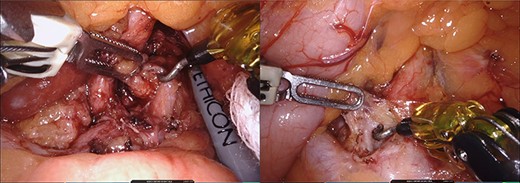

Initially, the left lateral segment of the liver was retracted and the gastro-hepatic ligament was divided to facilitate the identification of the right crus of the diaphragm. The local anatomy made difficult to access the celiac trunk through the gastro-hepatic ligament. The lesser sac was approached opening the gastro-colic ligament, and lifting up the posterior wall of the stomach using the robotic third arm. This maneuver also put in tension the left gastric artery making easier to reach the celiac trunk. All associated lymph nodes and fibrotic tissue that were crossing in front of the origin of the common hepatic and splenic artery were removed (Fig. 3). The dissection continued along the common trunk (Fig. 4). Neural fibers were divided and the origin of the celiac artery was fully exposed free (Fig. 5). Postoperative course was uneventful and the patient was discharged the next day without any dietary restriction. The pain was managed with acetaminophen only after discharge. At 5 months follow up, the patient showed complete resolution of symptoms.

Arterial structures exposure. Legend: upper images: arterial structures before release of the MAL. Lower images: arterial structures during release of the MAL. S: stomach, CHA: common hepatic artery, CA: celiac artery, LGA: left gastric artery and SA: splenic artery.